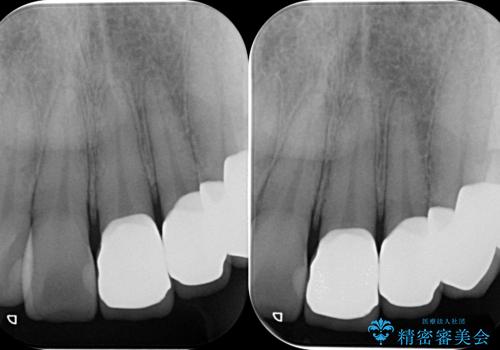

視診、X線写真より前歯に発生した大きな虫歯が認められました。